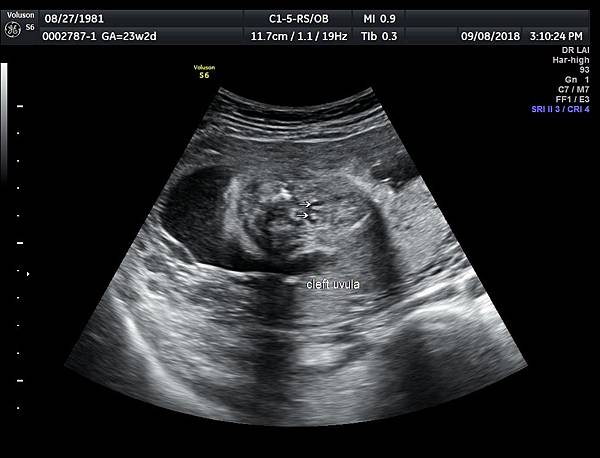

一個檢查如果要花很長的時間才能完成,這樣的檢查無法變成常規的篩檢方式,我已經在我的診所執行懸雍垂檢查一段時間,我檢查懸雍垂大約30 秒,前提是胎兒的臉最佳位置是側躺,其次是側躺偏向上,我的檢查步驟是上顎(含日後大門牙長出的位置)、舌頭、懸雍垂(= equal sign)(附圖1~8),如果超過60秒無法完成,只有兩個原因,一個是胎兒姿勢不適合或喉嚨羊水空間太小,這時候不要硬碰硬,只要先檢查其他部位,等待時機再回來即可,我的經驗是90%的cases都能順利完成這項檢查(肚皮厚的case真的是很難)。

有興趣的同業可以參考我的部落格備忘錄第119、120、127 及 236 這四篇,裡面有我做懸雍垂(uvula)的相關影像。